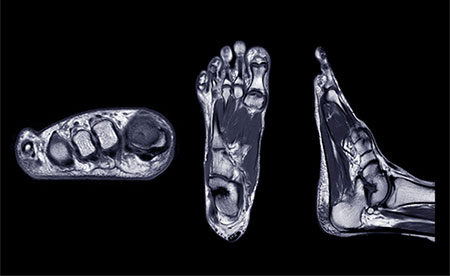

What an MRI Can Reveal About Your Ankle that X-Rays Miss

X-rays are excellent for detecting fractures, but do not show ligaments, cartilage, tendons, or subtle bone bruises. An MRI provides a detailed look at the soft tissues inside the ankle, helping reveal injuries that commonly cause chronic pain. These may include microtears of the lateral ankle ligaments, tendon injuries involving the peroneal tendons, cartilage defects known as osteochondral lesions, or inflammation and scar tissue trapped inside the joint.

Because these conditions often mimic the symptoms of a simple sprain, an MRI becomes a valuable tool when pain persists without a clear explanation.